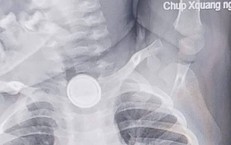

Nội soi gắp dị vật là vòng bạc trong dạ dày bé gái 5 tuổi

Y tế - 09/10/2025 18:30SKĐS - Mới đây, Bệnh viện Việt Nam – Thụy Điển Uông Bí tiếp nhận và xử trí thành công trường hợp trẻ 5 tuổi nuốt phải dị vật là chiếc vòng tay bằng bạc, dài khoảng 7 cm.